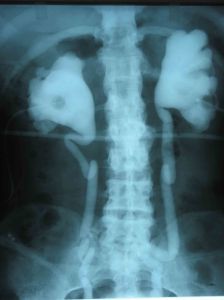

B超檢查方法簡單,無損傷,有助於診斷明確。還可以顯示積水腎剩餘腎臟組織的形態,也對了解尿路情況(腎盂、腎盞及梗阻近端輸尿管)有幫助。對胎兒尿路梗阻的有診斷價值。

積水腎剩餘腎實質厚度超過1.5cm者,腎有保留價值。